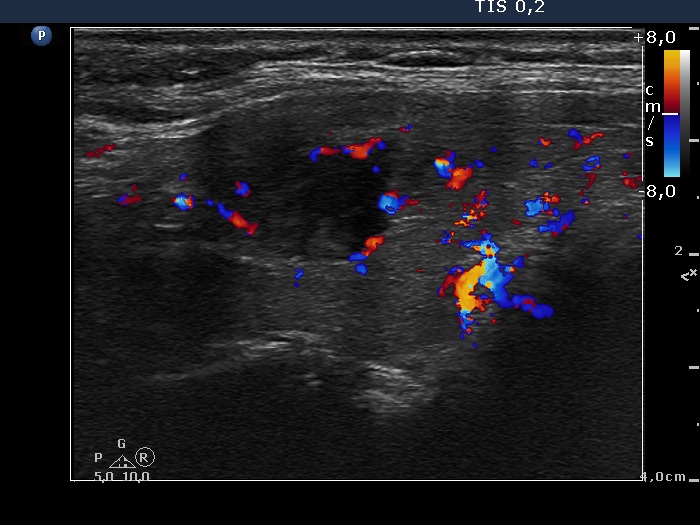

Right lobe, longitudinal scan

Right lobe, transverse scan, color Doppler mode. The nodule has intranodular vascularization.